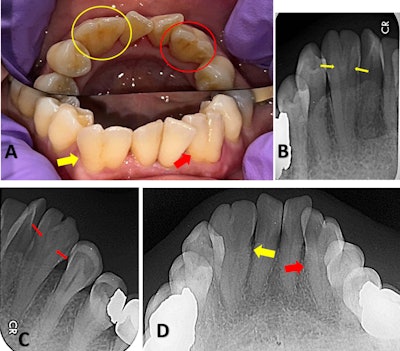

“Symmetrical fusion likely resulted from the simultaneous contact between developing tooth buds on both sides of the lower jaw,” they wrote. “… Each fused tooth exhibited a single root, suggesting that the fusion occurred before crown calcification, resulting in the complete fusion of both crown and root structures.”

(A-C) show axial CBCT images at the cervical, middle, and apical thirds of the root, respectively, of the fused right and left lateral incisors and canines exhibiting a single pulp chamber and a single root. (D, E) show sagittal CBCT sections demonstrating similar crown and root morphology of the fused lateral incisor and canine on both sides. Minor image noise was noted, partially obscuring fine internal details of the root canals; nevertheless, the diagnostic interpretation remained unaffected.